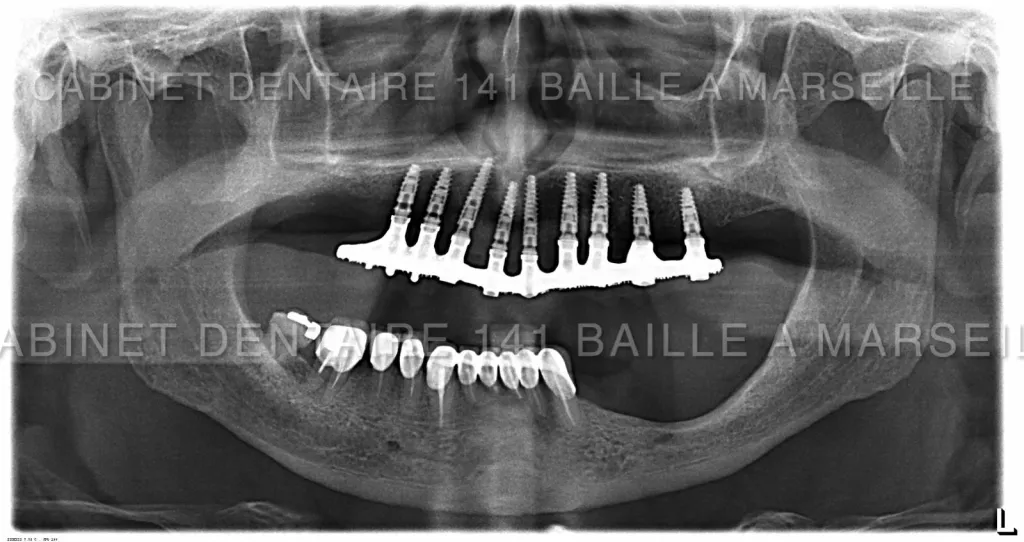

Nous sommes en mesure d'assurer la prise en charge de vos patients dans notre structure qui englobe la phase chirurgicale traitée naturellement en bloc opératoire stérile ,et sytème de traçabilité chirugicale aux normes hospitalières (Cycles prions à fractionnement de vide) ,pour tous les cas complexes intégrant implantations totales avec mise en charge immédiate.

Notre laboratoire intégré nous délivrera une prothèse immédiate qui permettra à votre patient de na pas avoir de gêne au niveau de sa vie sociale.

En général nous commençons à opérer le matin vers 9 h et la patient rentre chez lui vers 13h équipé d'une prothèse immédiate implanto- portée.